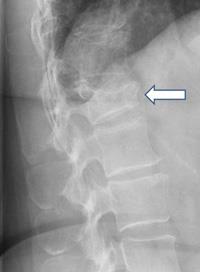

Spondylolisthesis is a condition in which one vertebra in the spine slips forward or backward over the one below it. It commonly affects the lower back, especially the lumbar spine, and can cause a range of symptoms that impact mobility and quality of life. Understanding the anatomy, pathology, symptoms, and treatment options for spondylolisthesis can help patients better manage the condition.

The spine consists of 33 vertebrae stacked on top of each other, separated by intervertebral discs that act as cushions. Ligaments and muscles provide stability and movement. In spondylolisthesis, the misalignment occurs when a vertebra slips out of place, often due to a defect in the bone (spondylolysis) or degeneration of the disc and joints that hold the vertebrae together.

Spondylolisthesis can result from congenital factors, trauma, degenerative changes, or repetitive stress. As the vertebra shifts, it may compress nerves in the spinal canal, leading to discomfort or pain. This condition is graded on the severity of the slip, ranging from mild to severe.